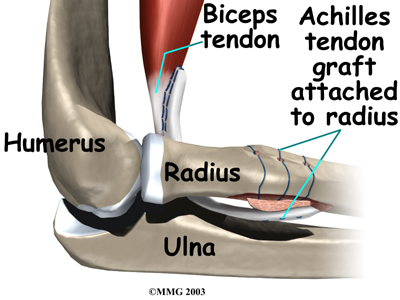

The attaches to a small bump on the radius bone of the forearm. This small bony bump is called the radial tuberosity. The radius is the smaller of the two bones between the elbow and the wrist that make up the forearm. The radius goes from the outside edge of the elbow to the thumb side of the wrist. It parallels the larger bone of the forearm, the ulna. The ulna goes from the inside edge of the elbow to the wrist.

If more than three or four weeks have passed since the rupture, the surgeon will usually need to make a larger incision in the front of the elbow. Also, because the tendon will have retracted further up the arm, graft tissue will be needed in order to reconnect the biceps to its original point of attachment on the radial tuberosity.

The surgeon then prepares a graft of tissue to lengthen the retracted biceps tendon. Some surgeons use a piece of hamstring tendon for the graft. Others use a section of the Achilles tendon where it attaches to the heel. This type of graft is usually an allograft, meaning that the tissue is taken from a cadaver (human tissue preserved for medical purposes).

When the is used, the surgeon leaves a small piece of the heel bone attached to the piece of tendon. Small holes are drilled into the piece of bone. Sutures are woven through these holes and will later be used to secure the end of the graft to the radial tuberosity. In this way, the graft will have a bone-to-bone connection that heals together. The healed bone solidly fixes the the graft to the radial tuberosity. After the graft is in place, its top end is then stitched over the front of the biceps muscle.

Next, the lower end of the graft is passed between the radius and ulna, exiting through the second incision that was made on the back of the forearm. The sutures from the bony end of the graft are threaded into holes that were drilled into the rim of the radial tuberosity earlier. The surgeon ties the sutures, to the radius.